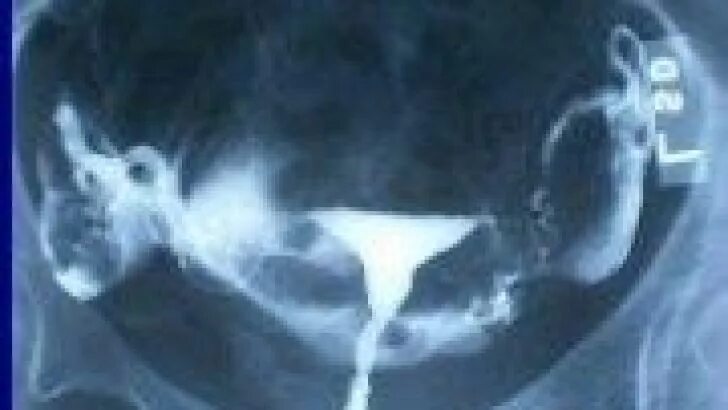

Проходимость маточных труб под наркозом